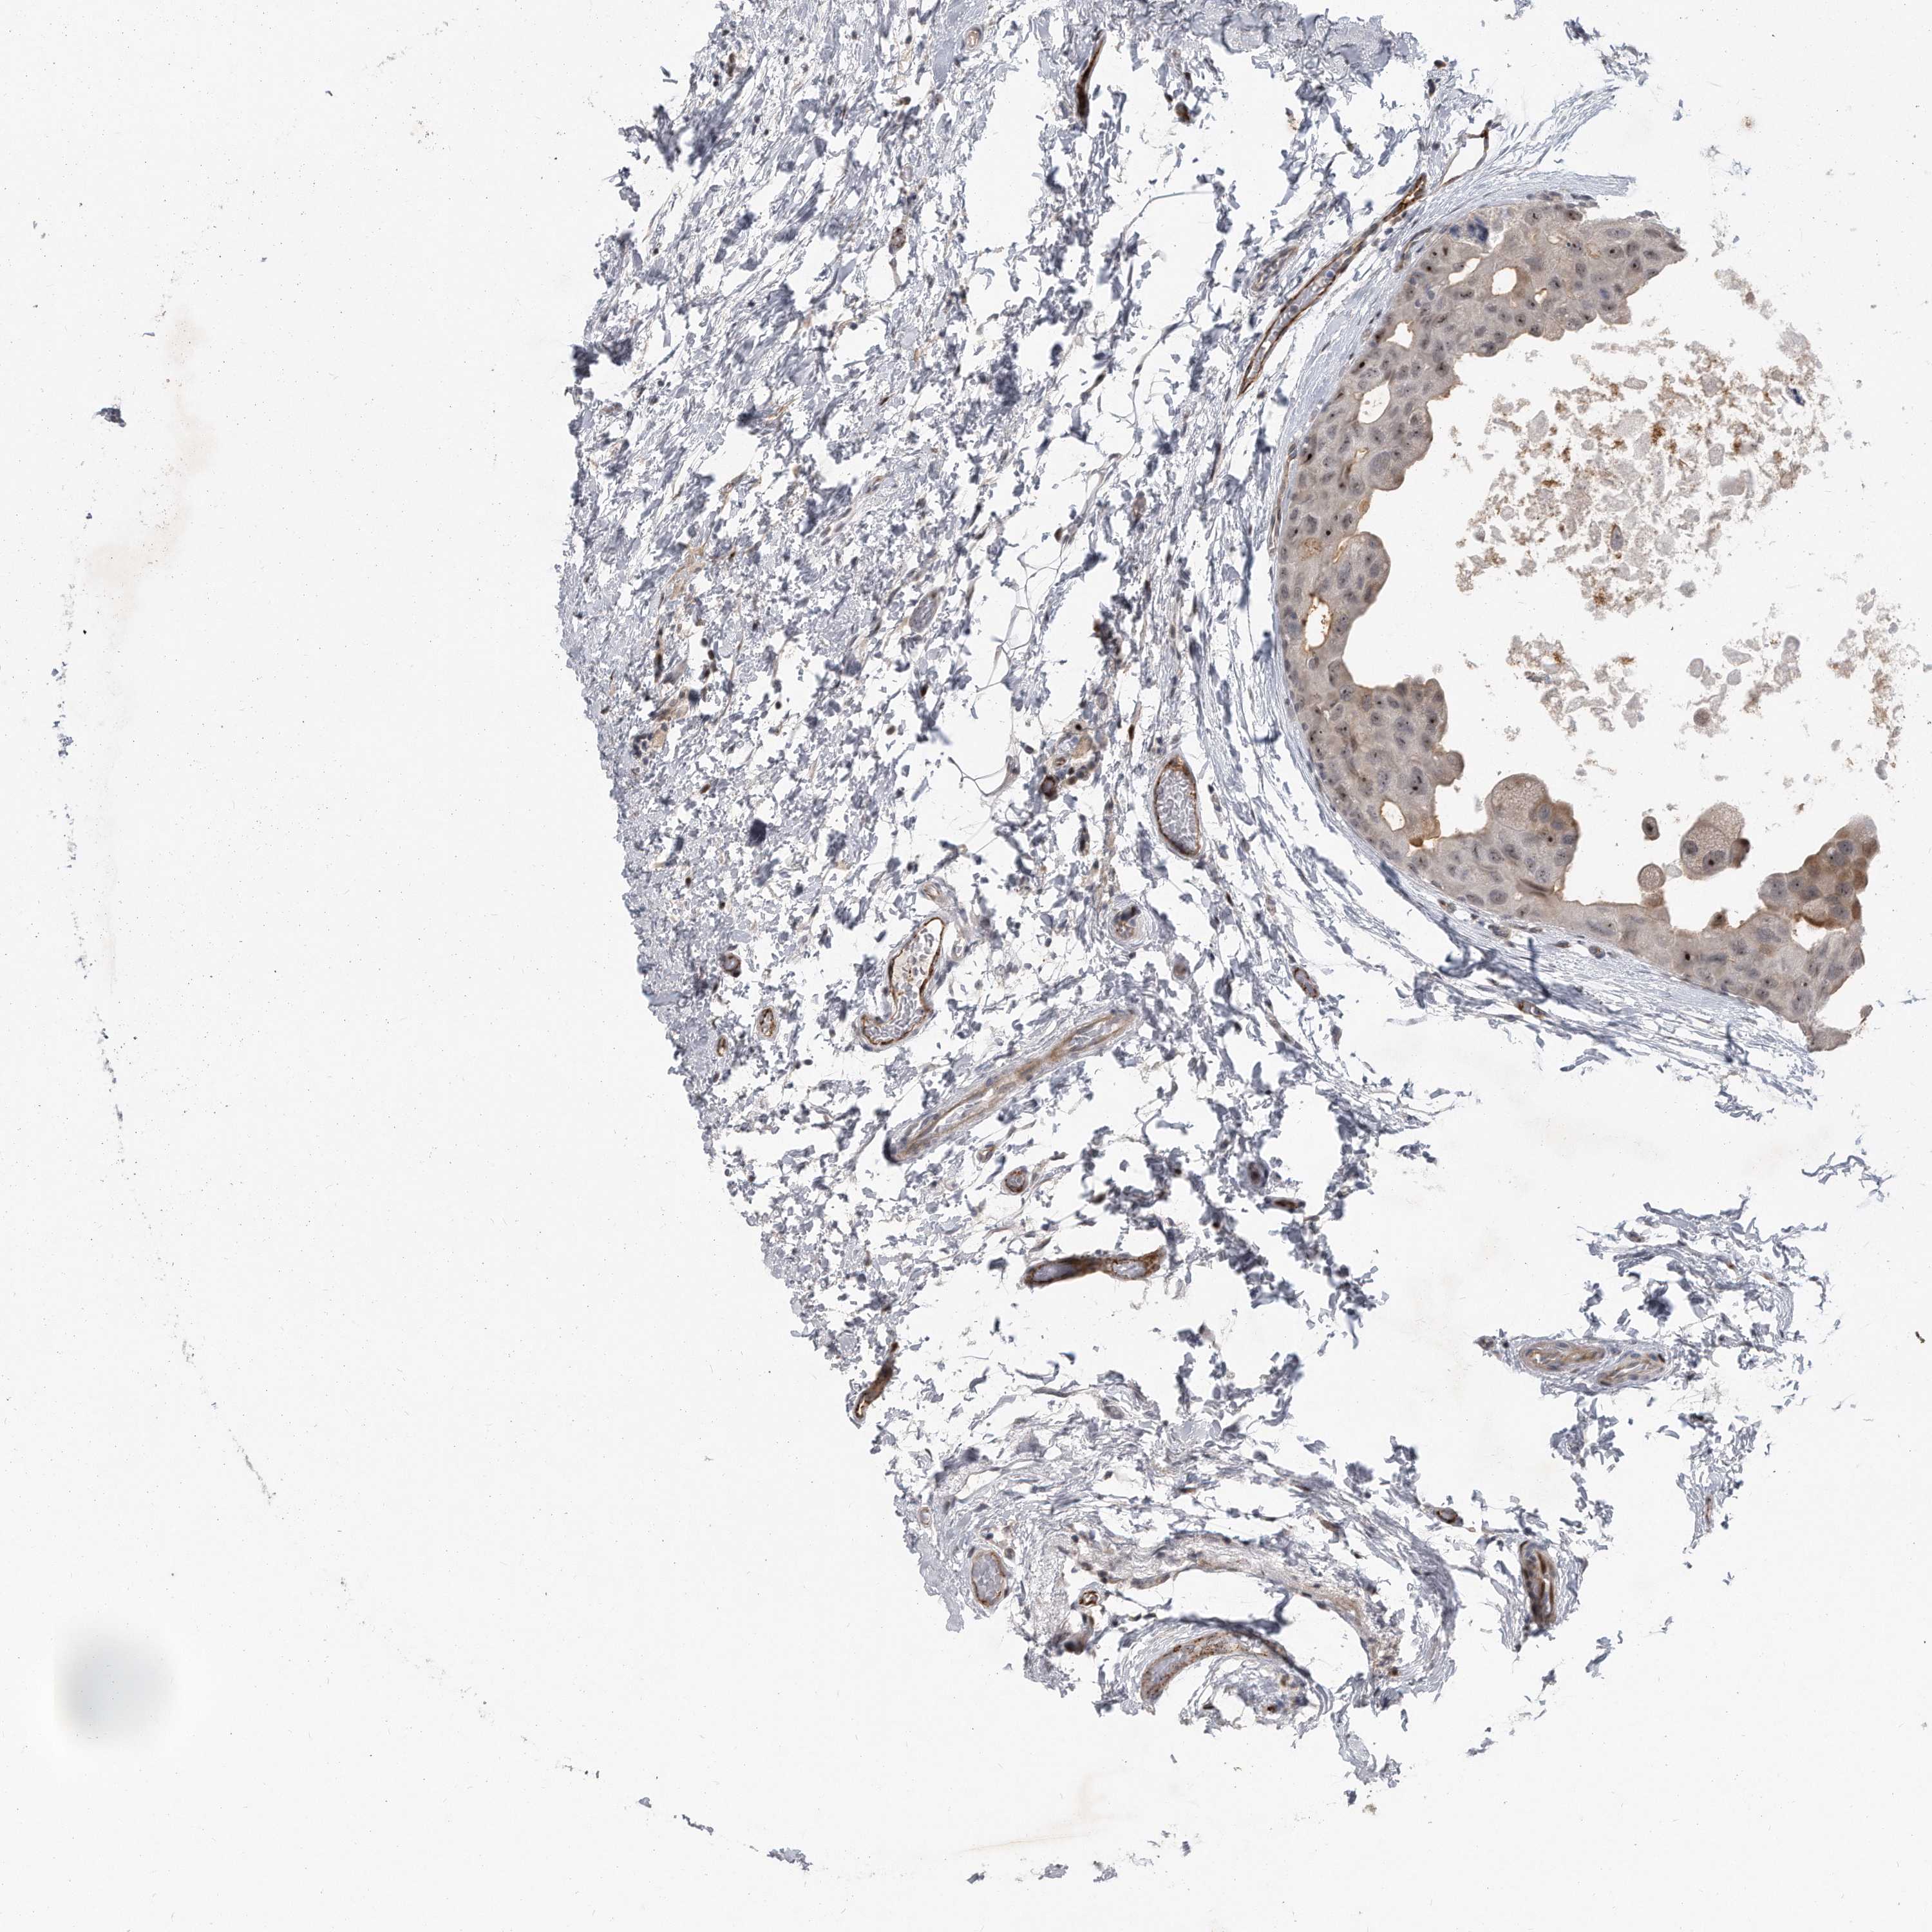

CANCER BREAST CANCER Show tissue menu

BRCA TCGA BRCA VALIDATION PROTEIN EXPRESSION

ANTIBODIES

AND

VALIDATION